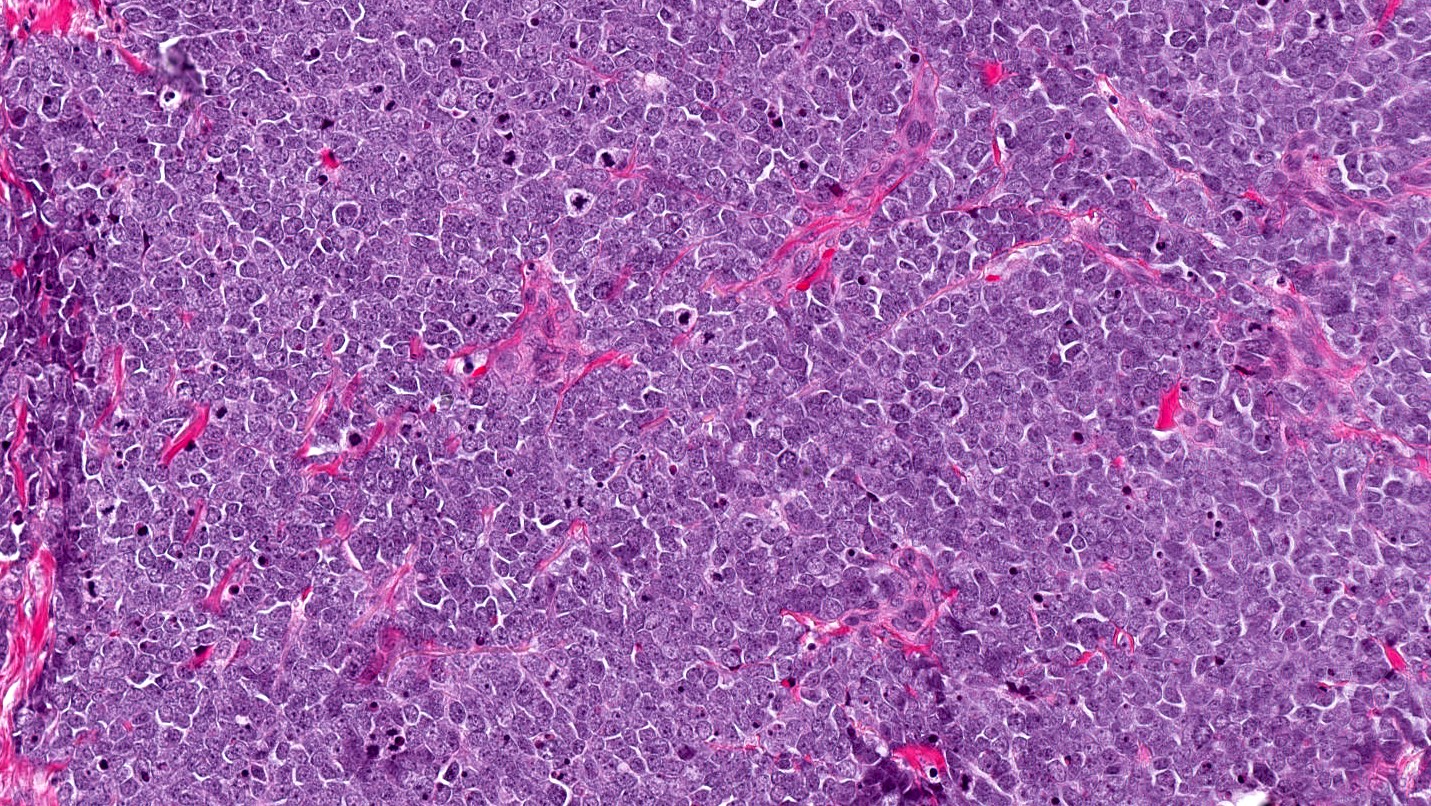

Microscopic (histologic) description

- Expansile, nodular or diffusely infiltrative tumor within the dermis, variably in subcutis

- Variable mixture of nodules, sheets, nests and trabeculae of neoplastic cells

- Intraepidermal tumor (or component) is occasionally present

- Generally, small round blue cell tumor with high N:C ratio, round / oval nuclei, finely dispersed chromatin (salt and pepper), indistinct nucleoli and scant cytoplasm

- Conspicuous mitoses and apoptotic bodies

- Variable nuclear molding and crush artifact

- Majority of cases display pure neuroendocrine morphology (pure Merkel cell carcinoma)

- Minority of cases feature neuroendocrine and other elements (combined Merkel cell carcinoma) such as divergent differentiation (e.g. squamous, sarcomatoid) or intimate association with other cutaneous neoplasms (most commonly in situ or invasive squamous cell carcinoma)